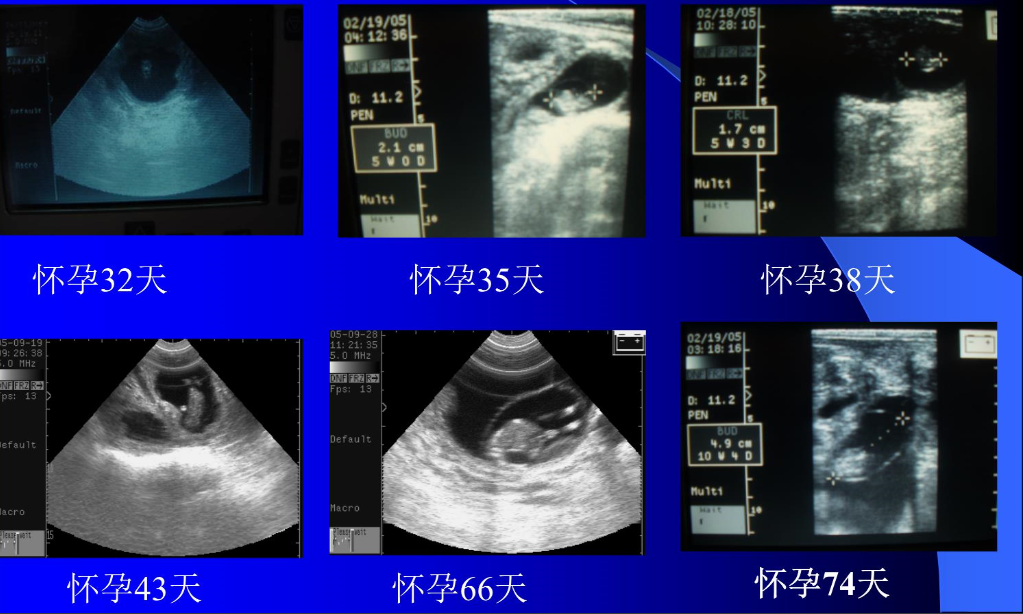

超声的实际应用包括妊娠状态的早期评估、怀双胎的母牛的识别、卵巢和子宫病变的检测以及胎儿性别的确定。这些应用中的每一个都为提高牛场的母牛繁殖效率提供了测试结果的准确性是,大多数兽医学生被教导超声波是牛繁殖工作的辅助技术。然而,超声成像的信息收集能力远远超过直肠触诊。从事母牛繁育的兽医老师和牛场技术老师使用超声波进行常规生殖检查的推广教学计划是该技术快速应用于母牛繁育行业的关键一步

经直肠实时超声在牛繁殖研究中的应用代表了一项技术突破,彻底改变了生殖生物学知识。通过超声成像产生的新研究信息阐明了牛复杂生殖过程的性质,包括卵巢卵泡动力学、黄体功能和胎儿发育。超声技术在母牛繁育的早期整合包括诸如经阴道卵泡抽吸和卵母细胞回收等应用,以及作为胚胎移植程序的补充技术